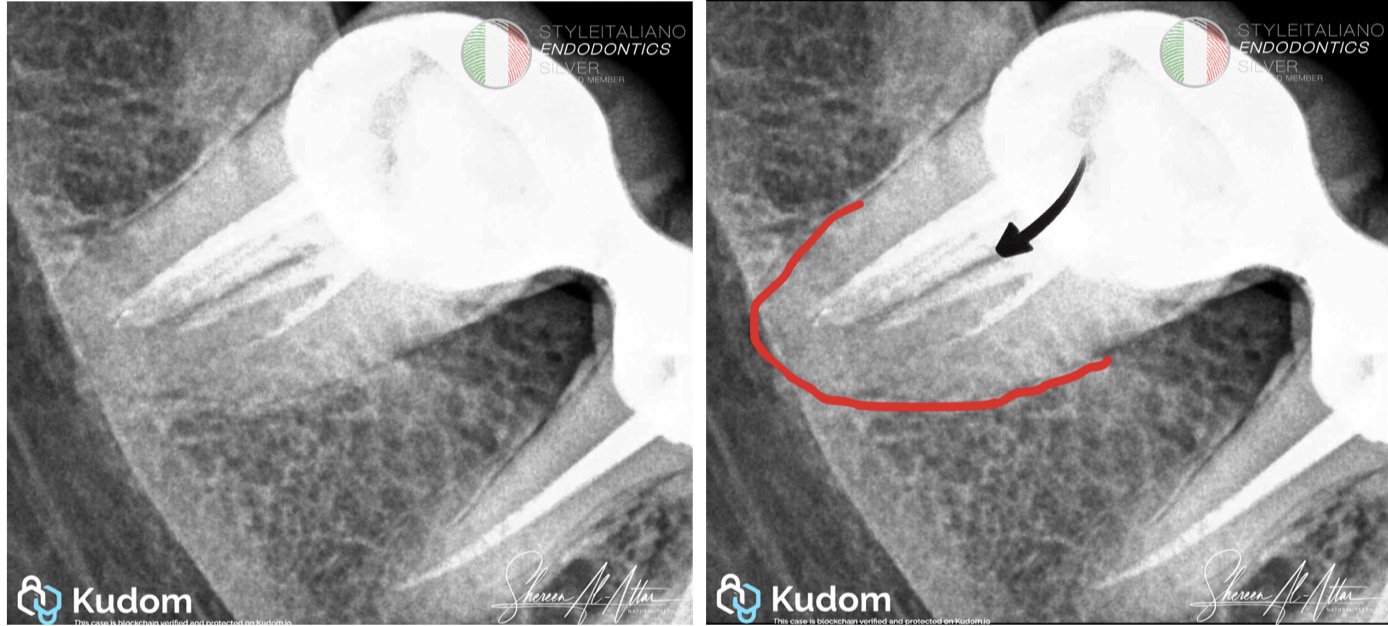

From the initial periapical radiograph of tooth #47, the presence of a single root outline associated with a furcation-like radiolucent line raised strong suspicion of a C-shaped canal system. Such radiographic features have been consistently reported as key indicators of C-shaped morphology in mandibular second molars [1,3]. This diagnostic insight guided the decision to adopt a retreatment protocol emphasizing enhanced coronal access, ultrasonic assistance, and activated irrigation to compensate for the limitations of mechanical instrumentation.